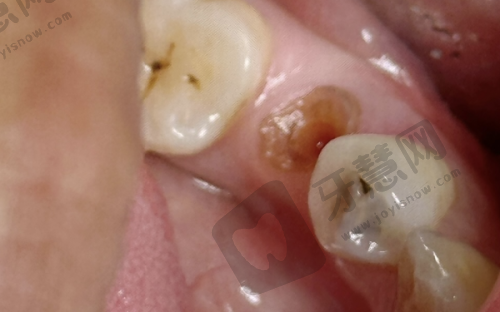

福州牙丽爱口腔门诊部成立于[具体成立年份],规模适中,诊疗环境舒适。设有多个科室,包括口腔内科、口腔外科、口腔正畸科、口腔修复科等。口腔内科擅长治疗各种牙体牙髓疾病、牙周疾病等,通过精良诊断技术和治疗方法,有效缓解患者疼痛,修复口腔健康。口腔外科能开展各类拔牙手术、口腔颌面外科手术等,医生技术娴熟,确保手术安心和成效。口腔正畸科专注牙齿矫正,采用多种精良矫正技术,如隐形矫正、固定矫正等,帮助患者改善牙齿排列不齐问题。口腔修复科为患者提供牙齿修复服务,如烤瓷牙、全瓷牙、活动假牙等,修复牙齿美观和功能。